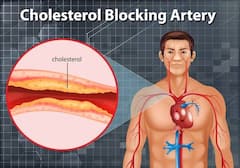

Heartburn in Pregnancy: प्रेग्नेंसी में इन कारणों से हो सकती है हार्टबर्न की समस्या, इस तरह पाएं छुटकारा

प्रेग्नेंसी के दौरान महिलाओं को कई तरह की समस्याओं का सामना करना पड़ता है. इन्हीं समस्याओं में पेट में गैस, बदहजमी, अपच, कब्ज जैसी परेशानी शामिल है. यह सभी समस्याएं शरीर में हो रहे हार्मोनल बदलाव की वजह से होती है. दरअसल, गर्भावस्था के दौरान पेट में मौजूद एसिड फूड पाइप के जरिए वापस आता है. ऐसे में जलन की परेशानी गले और सीने में पहुंचने लगती है. इस परेशानी से राहत पाने के लिए आप कुछ घरेलू टिप्स फॉलो कर सकती हैं. आइए जानते हैं इन घरेलू टिप्स के बारे में- (Photo - Pixabay)